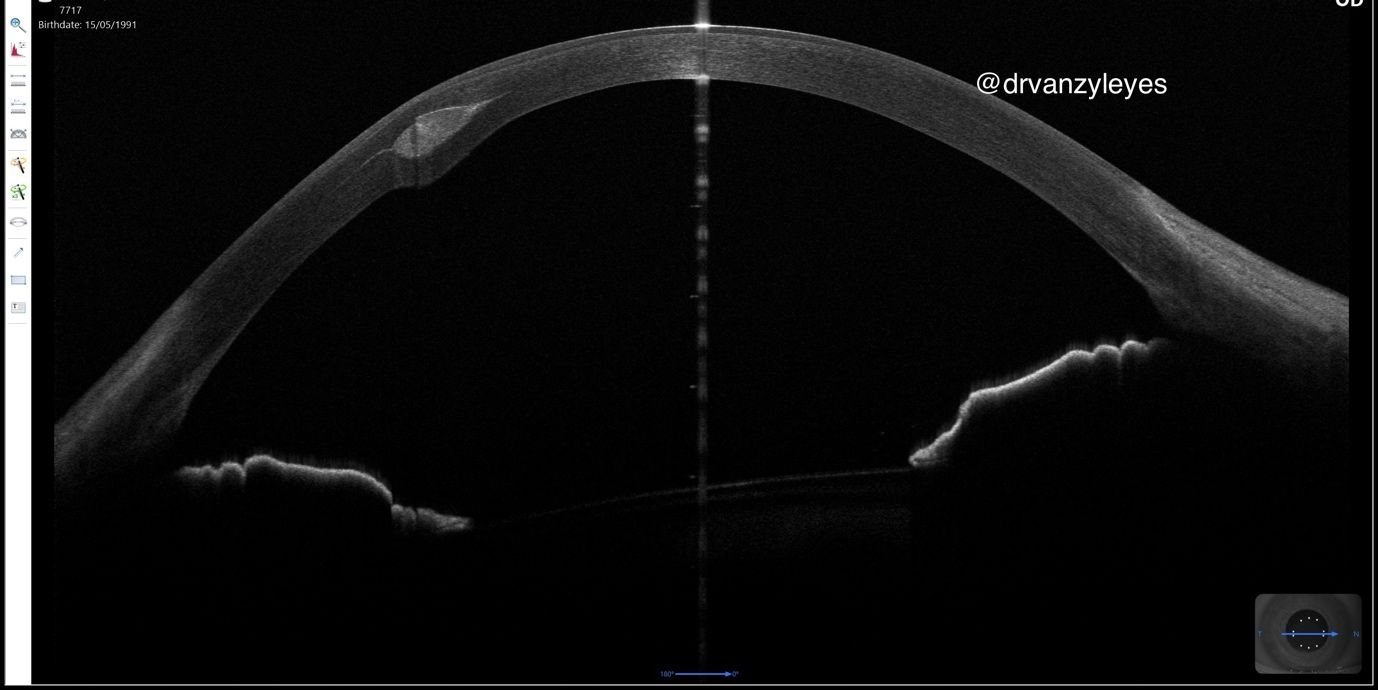

Scan of the cornea indicating a perfectly placed CAIRS keratoplasty segment